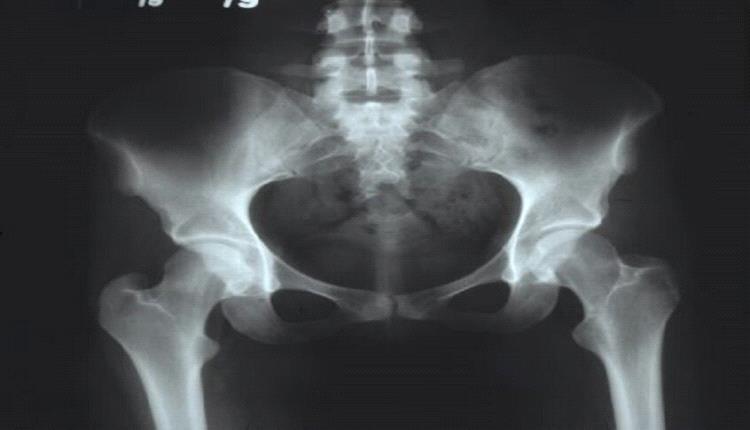

يوضح الدكتور أوليغ ساجنيكوف، أخصائي جراحة العظام، كيفية ظهور التهاب مفصل الورك، وما إذا كانت هناك سبل للوقاية من هذا المرض، ومن هم الأكثر عرضة للإصابة به.

ووفقا له، يُعدّ التهاب مفصل الورك أكثر أمراض مفصل الورك شيوعا. وهناك العديد من الأسباب التي قد تؤدي إلى الإصابة به، مثل: التشوهات الخلقية، والتشوهات المكتسبة نتيجة الإصابات أو الأمراض المختلفة، والتغيرات التنكسية الناتجة عن التقدم في السن، والنشاط البدني المفرط، وزيادة الوزن، والاضطرابات الهرمونية.

ويشير إلى أن من الأعراض المميزة لالتهاب مفصل الورك الشعور بالألم أثناء الحركة وتقييد نطاقها؛ وفي المراحل المتقدمة، قد يُلاحظ قصر في الطرف السفلي. وغالبا ما تكون العملية غير متماثلة، أي أنها تبدأ في أحد الجانبين أولا، ثم يتأثر الطرف الآخر نتيجة التحميل الزائد على المفصل السليم. وتُعدّ الفئة الأكثر عرضة للإصابة بالمرض هي الأشخاص الذين تزيد أعمارهم على 50 عامًا، وتُعدّ النساء أكثر عرضة للإصابة من الرجال.